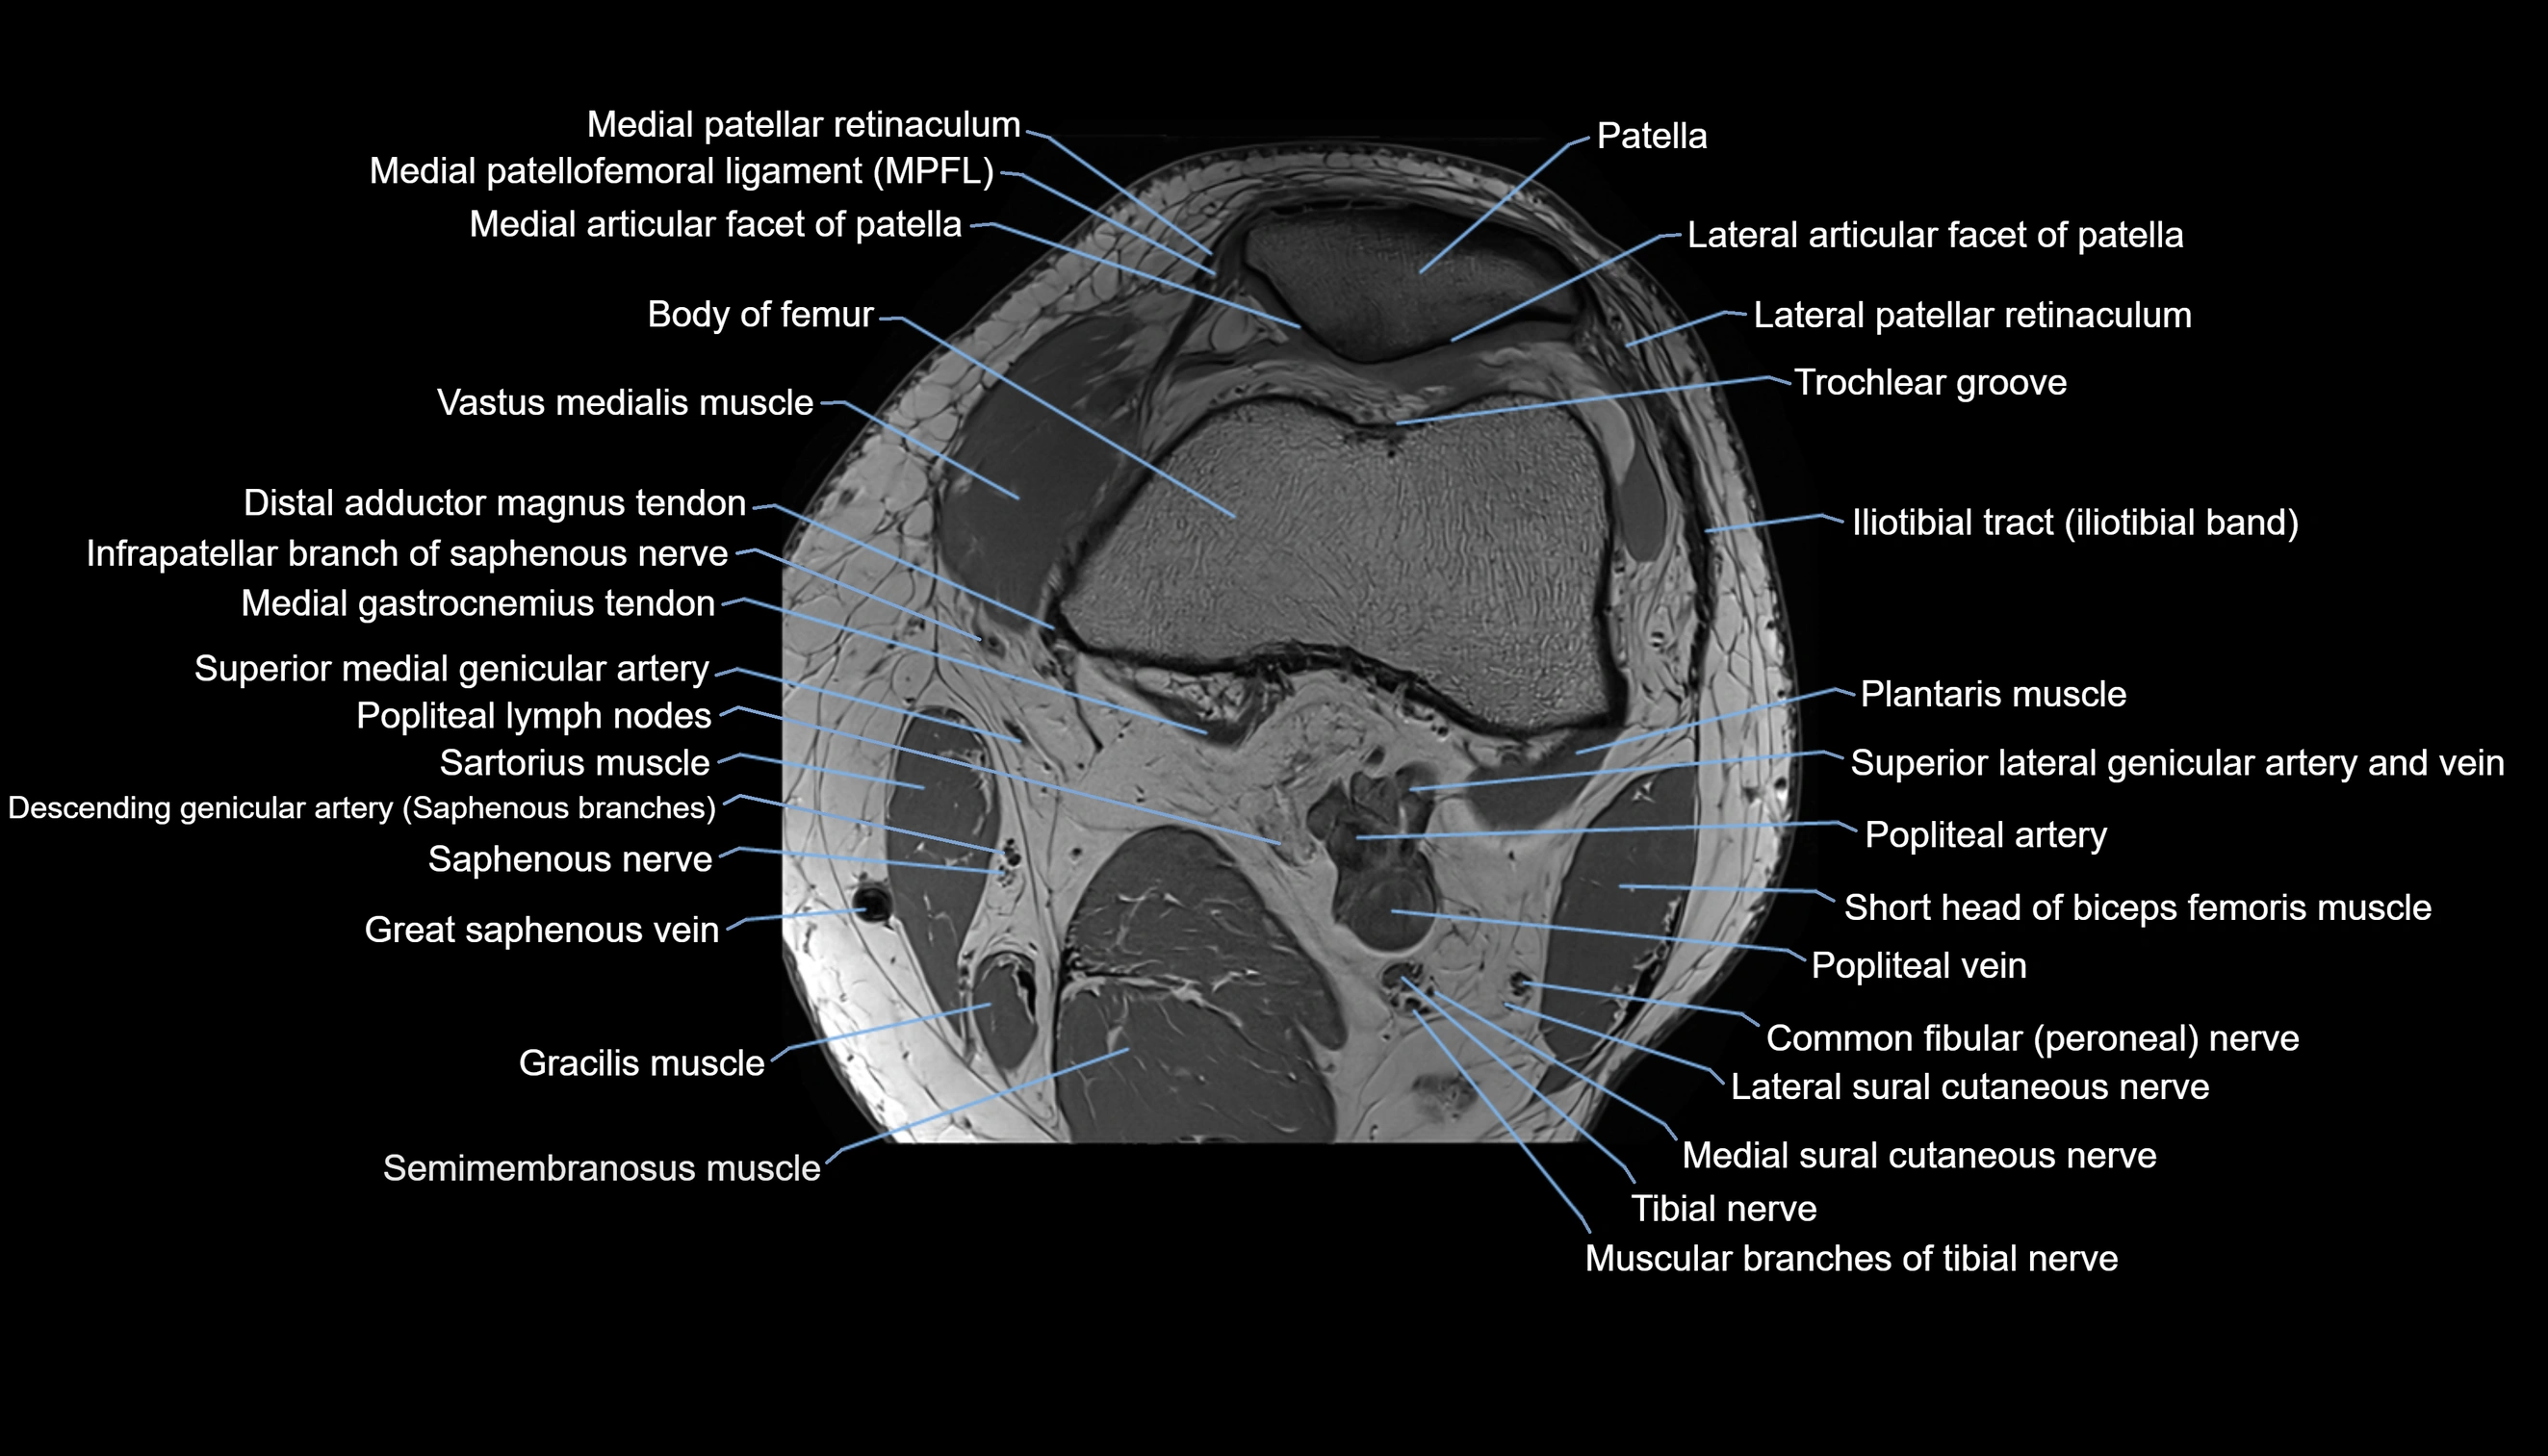

- Lateral articular facet of patella

- Lateral patellar retinaculum

- Lateral patellofemoral ligament

- Medial articular facet of patella

- Medial patellar retinaculum

- Medial patellofemoral ligament

- Patella

- Popliteal artery

- Popliteal lymph nodes

- Popliteal vein

- Sartorius muscle

- Semimembranosus muscle

- Tibial nerve

- Trochlear groove

- Vastus lateralis muscle

- Vastus medialis muscle

- great saphenous vein